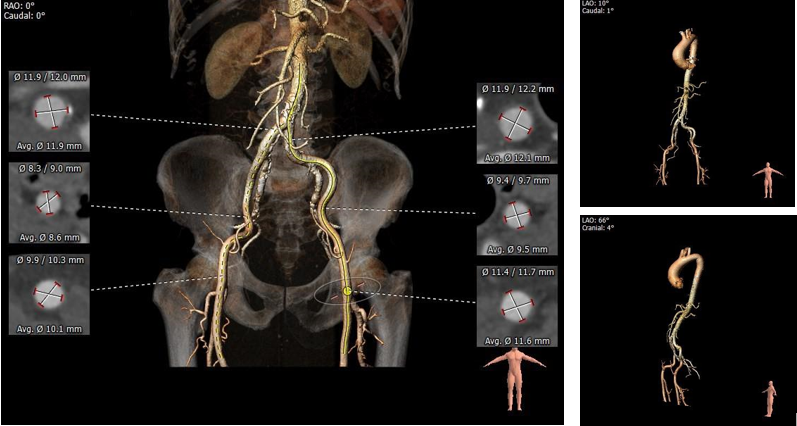

1.主动脉瓣瓣环周长88.6mm,平均周长径28.2mm。

2. Type0型二叶式主动脉瓣,左右冠脉不同窦,重度钙化,钙化分布均匀。

3.冠脉开口高度可,切线位测量右冠窦瓣叶略长于右冠开口下缘到瓣叶附着缘距离

4. 瓦式窦、窦管交界、升主动脉内径适中

5. 瓣环水平夹角63°,横位心,主动脉弓角度偏锐

6.双侧外周入路行走适宜,未见明显迂曲,右侧髂总动脉存在散在钙化,整体血管条件良好

主动脉根部评估:

根部概览

瓣上评估

外周血管及主动脉弓解剖